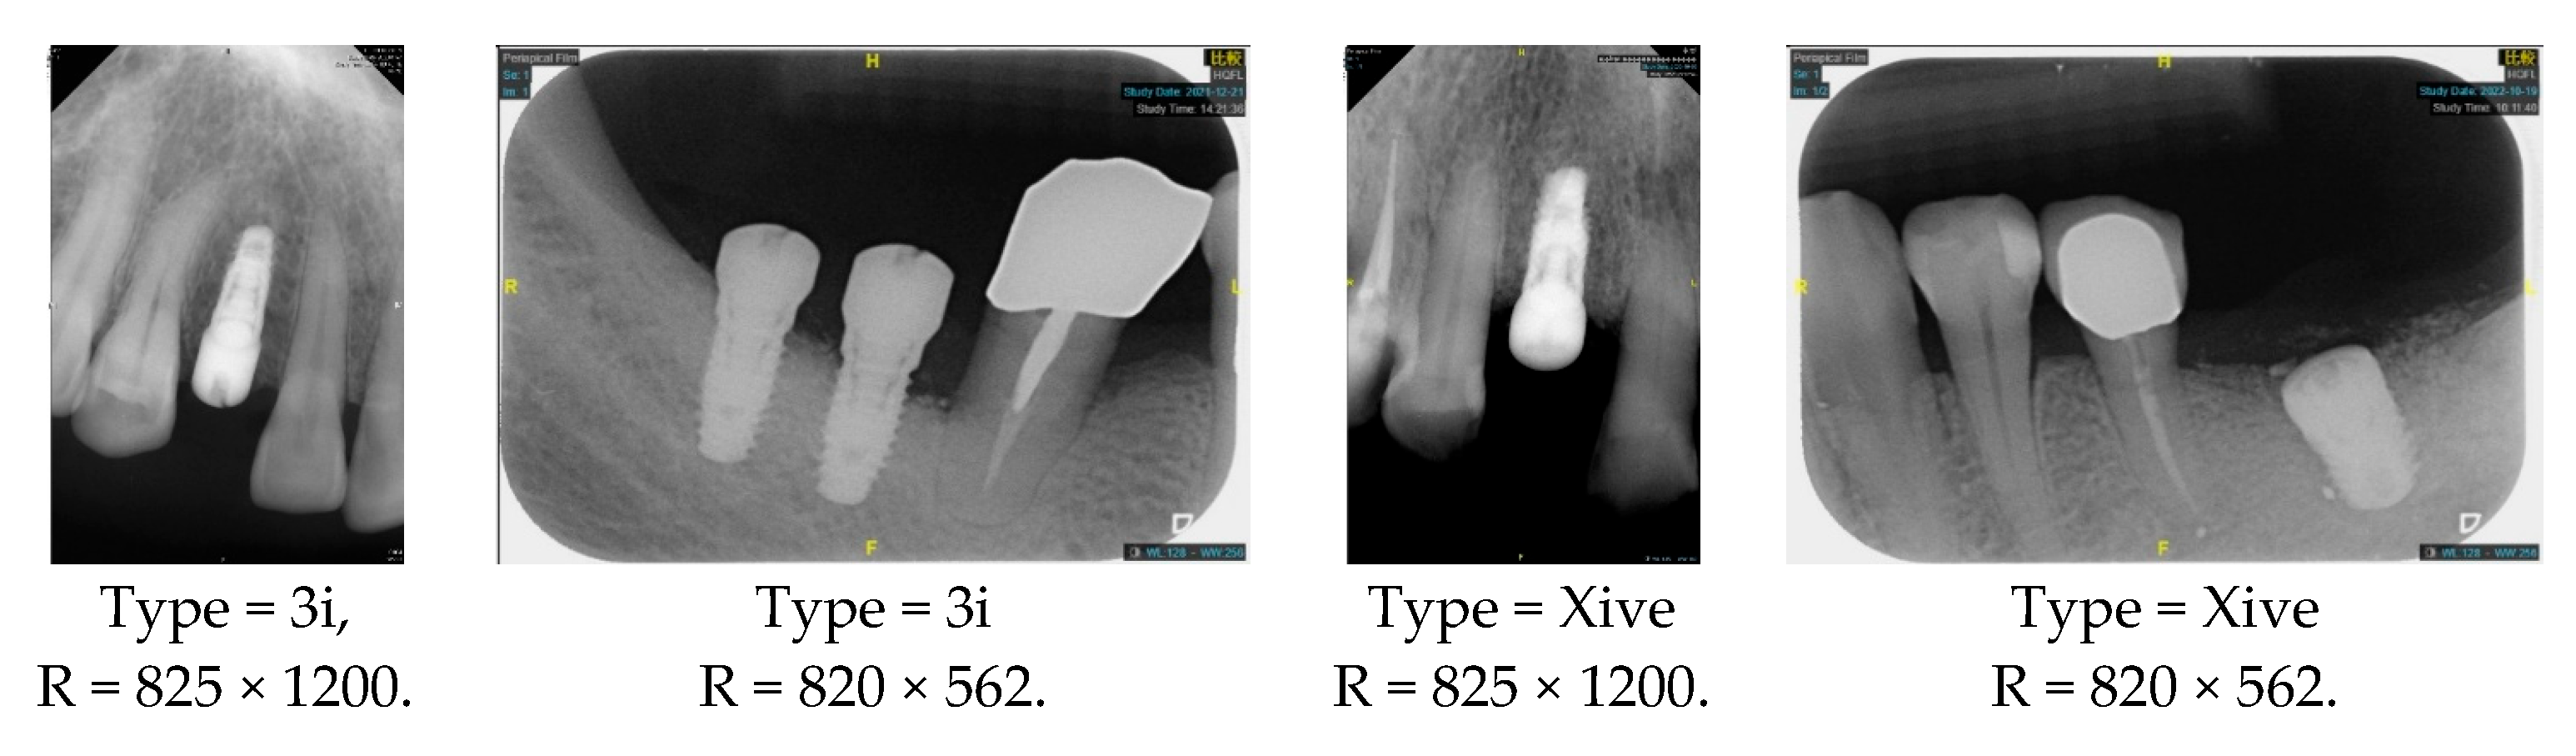

| Implant Brand | 3i | Xive |

| Dimension (D) | 3.25 mm/4 mm/5 mm/6 mm | 3.4 mm/3.8 mm/4.5 mm/5.5 mm |

| Length (L) | 8.5 mm/10 mm/11.5 mm/13 mm/15 mm | 8 mm/9.5 mm/11 mm/13 mm/15 mm/18 mm |

| Image Size | 825 × 1200 or 820 × 562 | Image format | DCI |

| The dataset includes two implant brands: 3i and Xive | |||

| 3i | 164 | Xive | 77 |